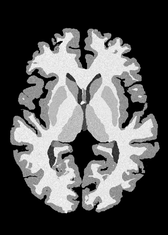

4.2 Registration to a 100 micron ex-vivo brain MRI volume

To showcase the efficacy of our method on real large scale images, we register a 250 in-vivo MRI image (Lüsebrink et al., 2017) to a 100 ex-vivo FLASH human brain volume (Edlow et al., 2019). This represents an inverse problem with more than 11.2B optimizable parameters (compared to 20M for clinical datasets), or 44.8GB of GPU memory. The entire problem does not fit on most GPUs, necessitating distributed multimodal registration. We optimize a composite transform - affine followed by a diffeomorphic mapping; details can be found in Section E.1. Multimodal deformable registration took 58 seconds on 8 NVIDIA A6000 GPUs, which is unprecedented at this resolution. Fig. 6 shows qualitative results, highlighting the ability to register highly detailed structures such as cerebellar white matter; these structures are not visible at macroscopic scales. The resultant advantages of performing registration at this scale can allow researchers to characterize the neuroanatomy at microscopic resolutions and allow morphometric analysis of cortical layers and subcortical nuclei among other structures.